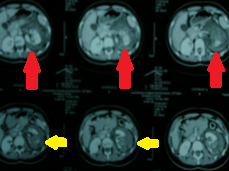

CT κοιλίας. Μεταστατικές εστίες στους σκελετικούς μύες δεξιά (κόκκινα βέλη) (Ευγενική παραχώρηση Dr. V. Penopoulos)